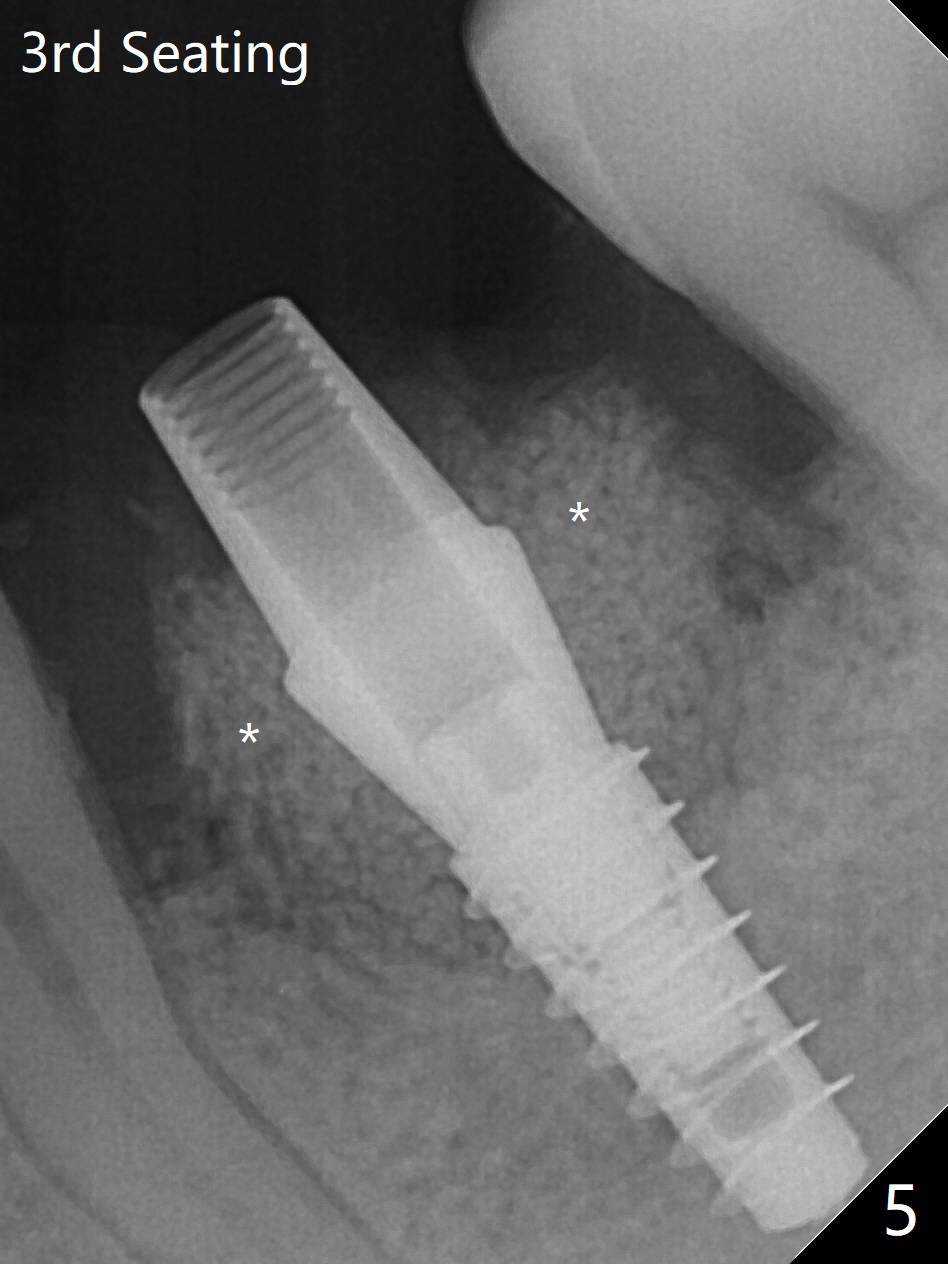

In spite of smoking reduction (1ppwk), the infection at #19, including buccal fistula (Fig.1 <) seems to be so severe that it affects pain threshold. Local anesthetics have to be added, including Bupivacaine IANB. When 4x10 mm drill is being applied, the patient feels pain. The plan is to use 4x11.5 mm drill as a final one. A 4x9 mm dummy implant is placed with 2.8 mm implant exposed (Fig.2 >), but it is subcrestal mesiodistally. Primary stability of a definitive 4.5x9 mm implant is satisfactory (Fig.3), but after initial bone graft, a 5x5.7(4) mm abutment is unable to be seated completely (<). Following 4.6 and 5.6 mm bone profile drills, the abutment remains incompletely seated (Fig.4). After fine turning, the abutment is fully seated; final round of bone graft (sticky bone) is placed mesiodistally (Fig.5 *) and buccolingually (Fig.6,7). It appears that there is tight fit between IBS implant and abutment. It is hoped that the excess bone graft with PRF is able to cover the coronal portion of the implant. If not, socket preservation should be done in this situation. In fact the implant is not placed lingual enough as compared to the design (Fig.6'). A 4.5 mm cortical drill should be used in a crown down fashion. In fact there is bone coverage coronally 5 months postop (Fig.8). Return to Prevent Molar Periimplantitis (Protocols, Table) No Deviation 12/14 Xin Wei, DDS, PhD, MS 1st edition 02/11/2020, last revision 06/30/2020